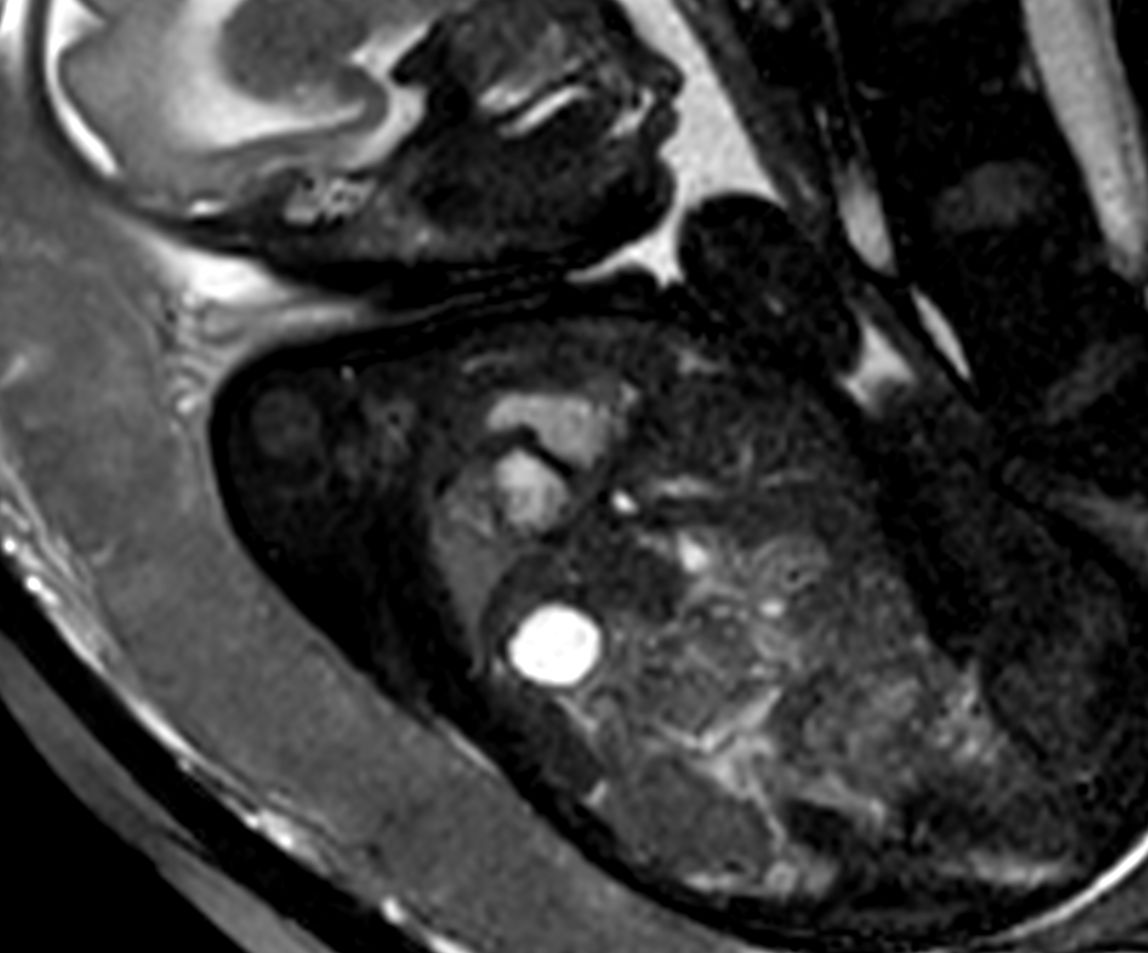

Morphology - bFFE short axis

Morphology - bFFE vertical long axis

Morphology - bFFE 4 chamber